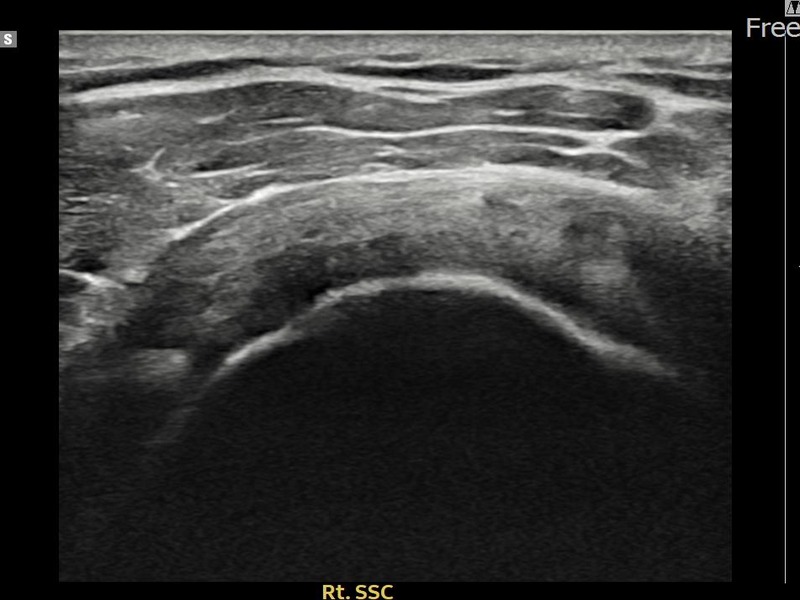

유ㅇㅇ님 · 우측 견갑하근건 관절면측 부분파열

우측 어깨 전방 통증과 팔 내회전 제한으로 내원하셨습니다. 초음파 검사에서 견갑하근건 관절면측 부분파열이 확인되었으며, 어깨인대 축소봉합술 후 힘줄 구조적 안정화가 이루어졌습니다.